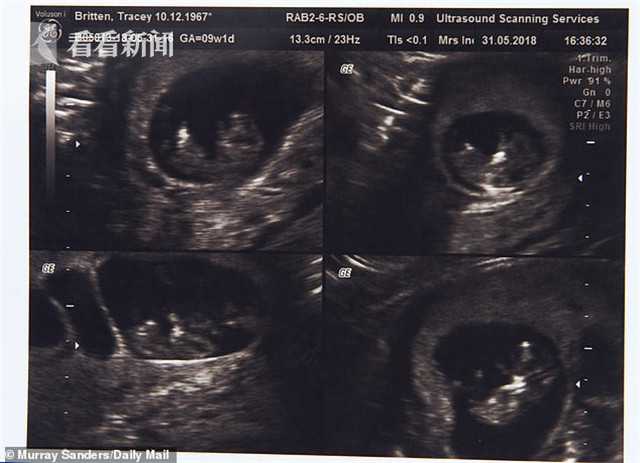

50歲時(shí),特蕾西與丈夫斯蒂芬花了7000英鎊(約合人民幣62317元)在塞浦路斯通過試管嬰兒手術(shù),懷上了四胞胎,其中三個(gè)是女孩,一個(gè)是男孩,三個(gè)女孩中還有一對(duì)是同卵雙胞胎。